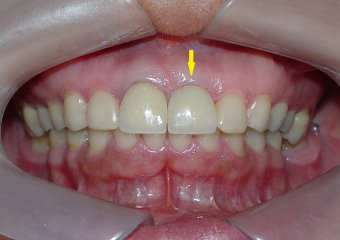

Sorriso final, do caso terminado em outubro de 2011

Sorriso Final, Controle em 2013